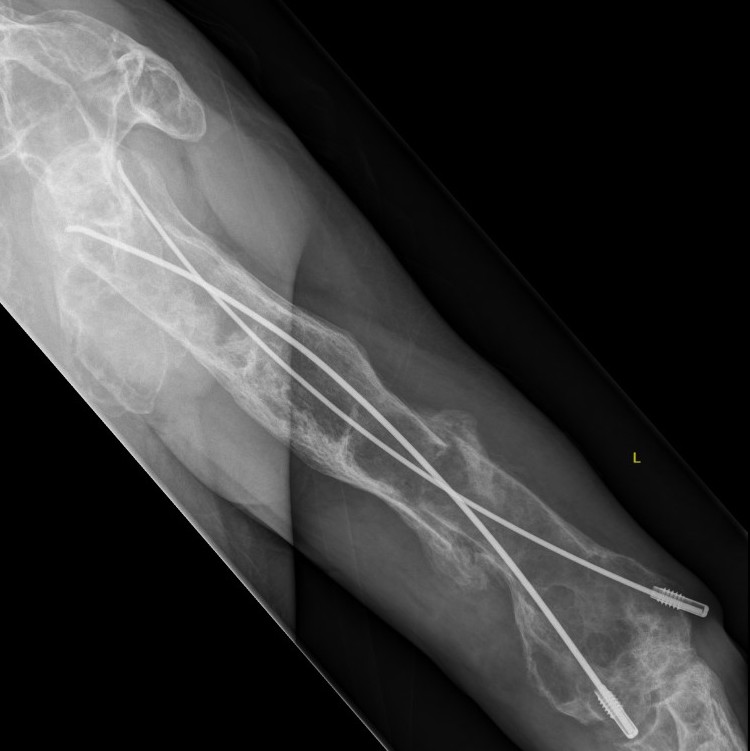

Coxa vara and Shepherd's Crook deformity of proximal femur

- Shepherd's Crook - anterior bowing of femur

Corrective osteotomy / Intra-medullary nailing

Mainstay of treatment

Ippolito et al J Orthop Traumatol 2023

- 24 patients with 34 femurs and 14 tibias requiring intra-medullary nailing

- mean age 32

- osteotomy and deformity correction often required

- nonunion / delayed union / implant failure in 5 cases

Proximal femur coxa vara and shepherds crook deformity

- 11 cases

- initial osteotomy correction of coxa vara and fixation with hip plate

- later osteotomy and correction of shepherds crook / femoral bowing and insertion reconstruction nail

- improved pain and gait

- significant blood loss at both stages